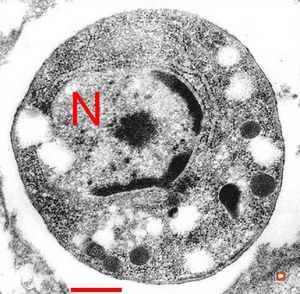

M,10y. | herpetic encephalitis